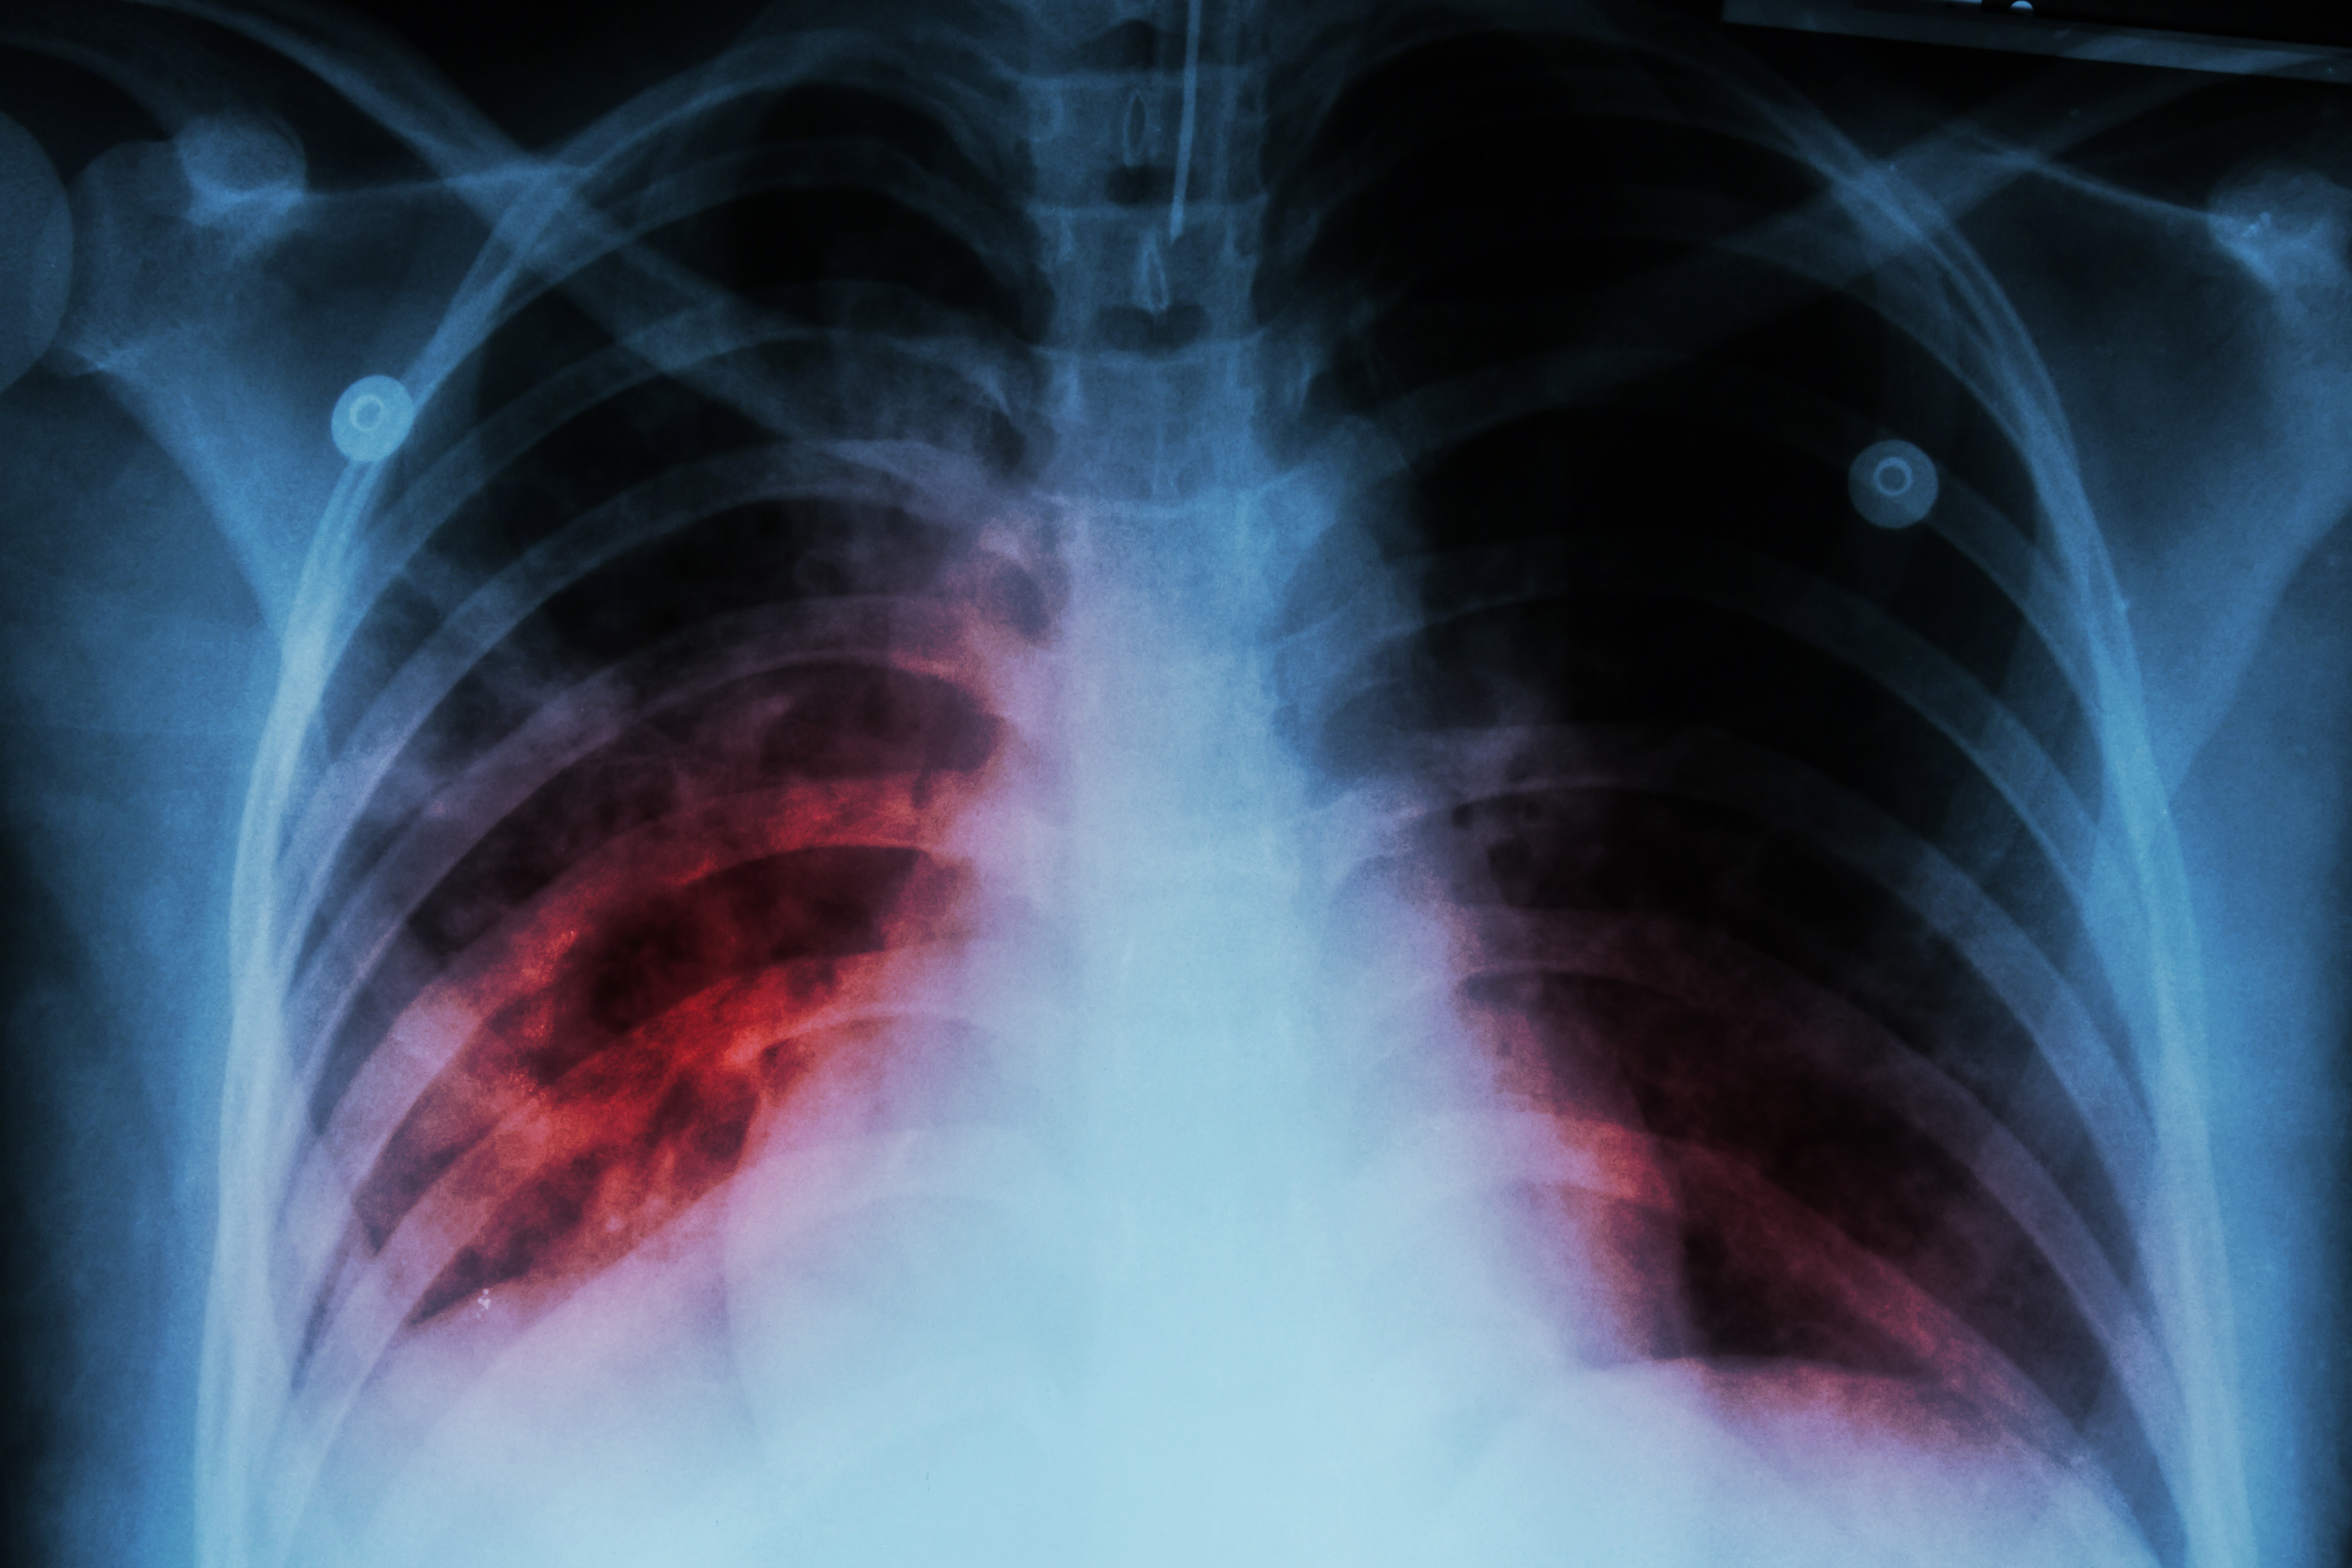

Chest x-ray showing lung inflammation caused by M. tuberculosis infection.